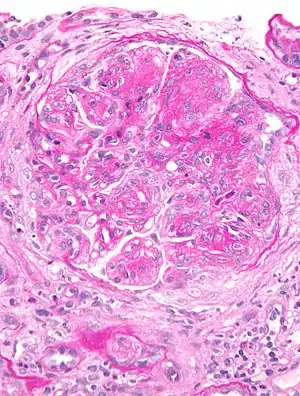

| Micrograph of glomerulus in membranoproliferative glomerulonephritis with increased mesangial matrix and increased mesangial cellularity. Kidney biopsy. PAS stain. | |

The GBM is rebuilt on top of the deposits, causing a "tram tracking" appearance under the microscope.[6] Mesangial cellularity is increased.[7]